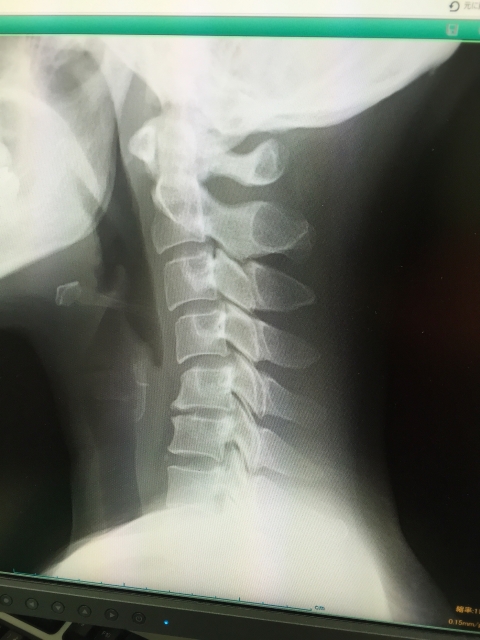

本来、若い人の首(頚椎)のラインは、前方に弓形(生理的前弯)になっています。加齢とともにその自然な弓形のラインが少しずつ無くなってしまい、まっすぐになることで頭が首の前に出ます。

これがいわゆる「ストレートネック」または「スマホ首」です。